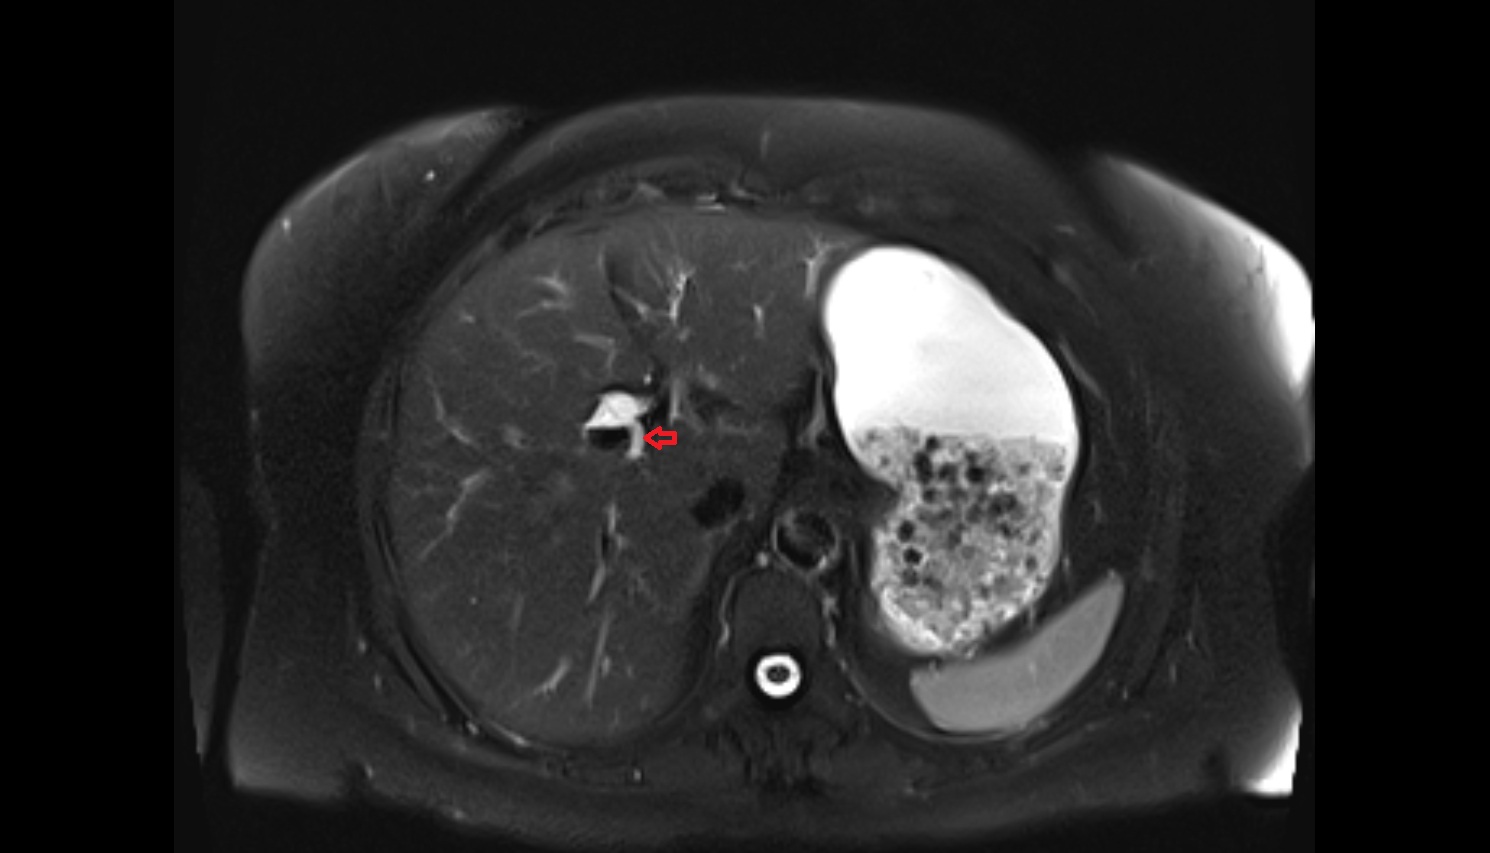

- Liver

- Spleen